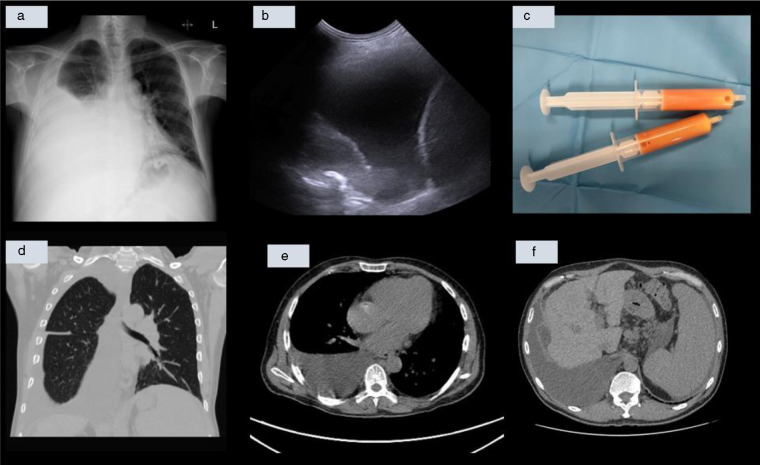

Portal Hypertension: An Uncommon Cause of Chylothorax and an Atypical Association With Systemic Sclerosis

门脉高压:乳糜胸的一个不常见原因和系统性硬化症的非典型关联。